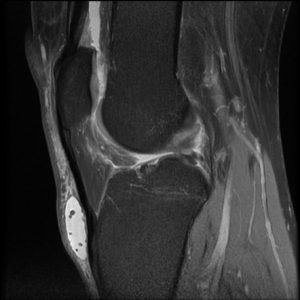

Figure 3 demonstrates a fluid filled bursa over the ligament and distal patella. On this fat suppressed image, the bursa manifests high signal intensity (white), due to the relatively pure fluid content.

In figure 4 the site of inflammation is lower in the bursa than that seen in figure 2. The fluid is again high signal intensity; however, there are multiple small hypointense bodies within it, likely representing some intrasynovial debris.